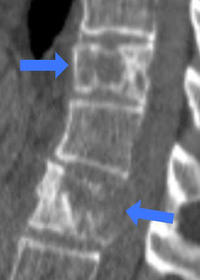

この画像は、乳がんから脊椎(背骨)に転移した患者です。通常脊椎は、ダルマ落としのように骨が連続して首からお尻まできれいに並んでいます。しかし、転移すると骨が溶けてしまい=図1=、今にも折れそうにスカスカになってしまいます(青い矢印部分は骨が溶けている)。このように画像でも分かるくらいの大きな転移だと、痛みもかなりのものになります。